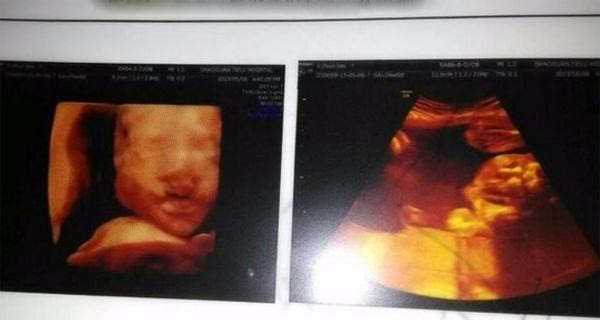

Ly Ly, thai phụ đến từ Trung Quốc, vốn là một vận động viên thể dục nên trong thời gian mang thai, cô vẫn duy trì được sức khỏe dẻo dai và không gặp nhiều triệu chứng bầu bí thường thấy như ốm nghén. Vậy nên, đến tuần thứ 24 của thai kỳ, Ly Ly mới đi khám thai rồi chết đứng khi nghe bác sĩ đọc kết quả siêu âm, xác định đứa trẻ trong bụng bị dị tật hở hàm ếch, môi trên của bé bị hở tới 0,7cm.

(Ảnh minh họa)